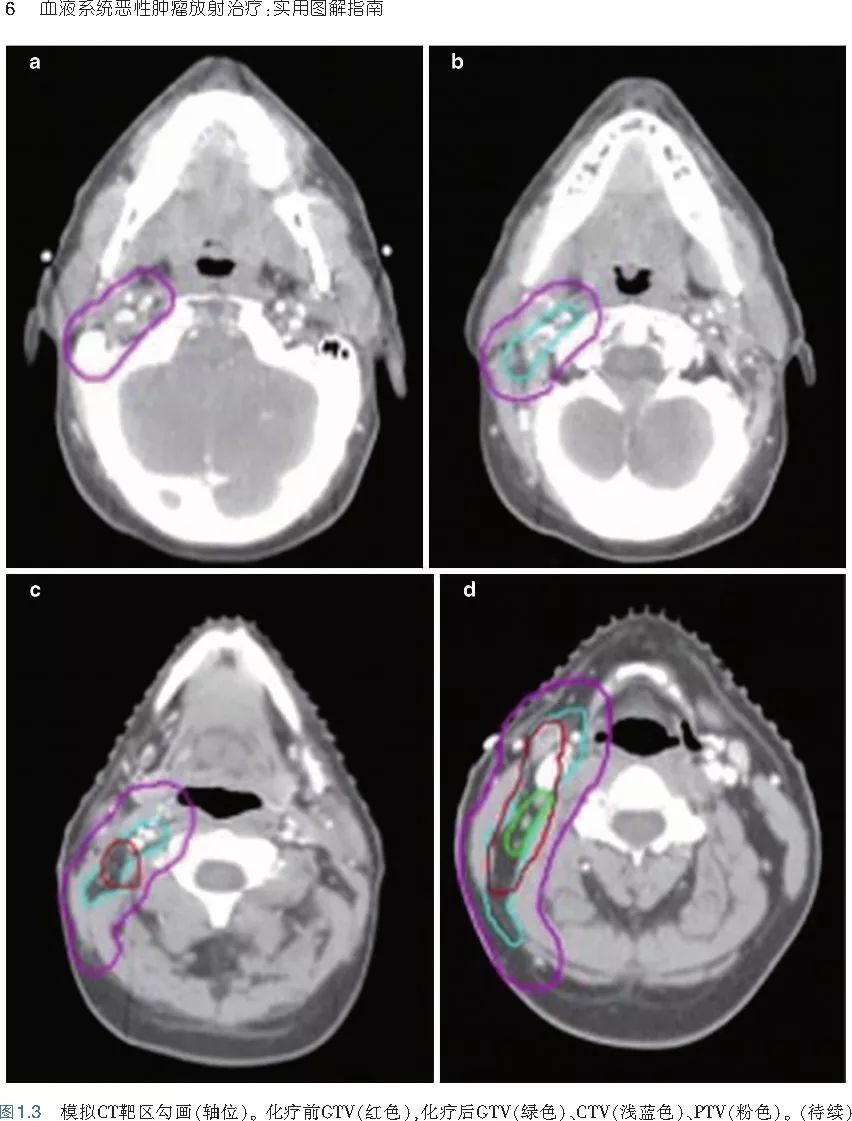

❤ 展开疾病诊断、病理描述及治疗方向的详细阐述,包含医学影像,图文并茂,深入浅出。

本书旨在帮助临床医生对常见血液系统恶性肿瘤疑难病例进行管理,包括霍奇金淋巴瘤、非霍奇金淋巴瘤和白血病患者,并通过多个病例进行阐述。案例讨论遵循标准格式,包括临床描述,其次是与诊断相关的病理描述和分期,然后详细讨论治疗选择。最后,确定治疗方案,并提供所使用的规划放疗技术/方式的图像。对放射肿瘤医生进行临床决策非常有帮助,对于血液病临床医生也有很好的指导作用。

近年来,放射治疗技术得到了迅速发展,调强放疗、图像引导放疗及其他新技术方法等,对恶性肿瘤治疗产生了巨大影响。现代放疗技术使精确定位、靶区勾画及给量成为可能,实现了肿瘤局控率和生活质量的双赢,对血液系统恶性肿瘤的临床治疗也产生了一定的影响。此书内容上不仅反映了血液系统恶性肿瘤综合治疗的进步,更是对其中放射治疗的新变化进行了系统、详细的阐述,这对当前血液系统恶性肿瘤放射治疗临床实践具有非常好的指导作用和参考价值。